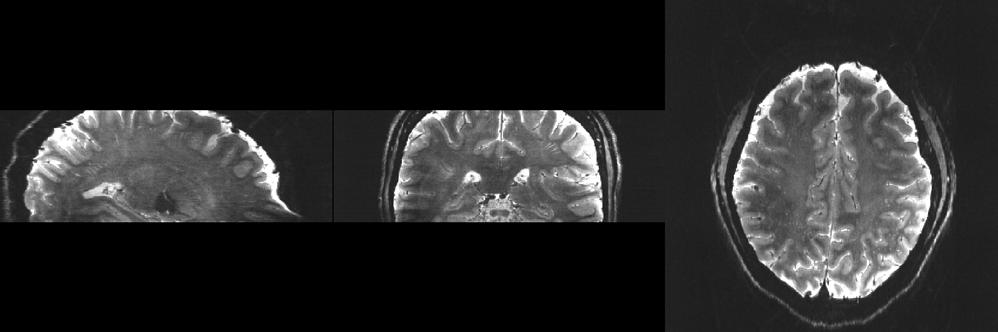

Next Gen 7T MRI Allows Neuroimaging with Unprecedented Precision

Conventional MRI scanners for clinical use generate images using magnets whose strength is measured at 1.5 Tesla (T) or 3T. At a limited number of locations across the world, clinicians and researchers have access to MRI scanners with much more powerful magnets operating at 7T. With the several dozen 7T machines located in the United States, imaging scientists can gain much higher resolution images, examining the tiny details that make up the architecture of the brain and body. However, there is still a ceiling to that resolution, as even with the most optimal scan parameters, features smaller than one to two millimeters vanish into the abstraction of the voxel, a three-dimensional pixel.

In December 2023, an international team of scientists including UCSF faculty member An (Joseph) Vu, PhD, broke that ceiling. Led by UC Berkeley professor and president of Advanced MRI Technologies, David Feinberg, PhD, MD, the team is a multi-institution collaboration with scientists from UCSF including Drs. An (Joseph) Vu and Pratik Mukherjee, UC Berkeley, Harvard, Siemens Healthineers (Erlangen, Germany), Advanced MRI Technologies (Sebastopol, CA), and MR CoilTech LTD (Glasgow, UK). Together, they constructed a next generation ultra-high resolution 7T MRI scanner, which achieves up to 10-fold increase in resolution over the current 7T standard, which is 50 times more detail than the hospital standard 3T scanners. With this new tool, functional images can now be captured with a voxel size of less than half a millimeter. This allows scientists to, for the first time, image functional clusters of neurons across

the entire brain, organized in cortical cell layers and cortical columns, opening up the study of a new realm of meso-scale local neurocircuitry.

Thanks to additional funding obtained by Drs. Vu, Feinberg, and Alexander Beckett, the NexGen 7T is now available to scientists across the Weill Neurohub consortium of UCSF, UC Berkeley, and the University of Washington, and as an international resource through the NIH BRAIN Initiative. The NexGen 7T MRI scanner is described in a Nature Methods article “Next-generation MRI scanner designed for ultra-high-resolution human brain imaging at 7 Tesla.”1

Although the NexGen 7T is not yet FDA approved, it has achieved remarkable breakthroughs in fast, high-resolution neuroimaging by virtue of several key advancements: an extremely powerful head gradient system, the first 128 channel receiver systems integrated into a 7T scanner, and several universally optimized RF pulse sequence protocol.

The new head-only magnetic gradient coil design that is an order of magnitude more powerful than those in

NexGen 7T 0.6 mm isotropic diffusion images (b=0 s/mm2) depicting fine anatomical structures including hippocampal layers and perivascular spaces.

commercially available 7T scanners. This advancement in gradient performance was achieved with a novel 3-layer wire winding design instead of only two layers. The faster and stronger the magnetic gradients are, the faster the MRI data can be encoded, fighting the clock of T2 signal decay and blurring. There were a lot of physics challenges to achieve such strong and fast gradients. In addition to the need to minimize peripheral nerve stimulation effects, the mechanical forces interacting with the field and the sound pressure levels both increase as the main magnetic field gets stronger. These challenges were detailed in “Acoustic noise reduction in the NexGen 7 T scanner.”2 For all these reasons, the scanner needed to be designed at a system-wide level, factoring in RF coil design, gradient coil design, and magnet design.

Another breakthrough came via the development of 64 channel and 96 channel receiver arrays coupled with the 128-channel receiver system, vastly improving on the standard 32 channel system in terms of SNR and the ability to accelerete the imaging. As the number of receiver channels increases, the size of the individual coil loops in the head coils become smaller, which in turn provides higher sensitivity and improved ability to accelerate data acquisition for fast, ultra-high resolution functional and structural MRI.

The improvements are not only related to hardware, as RF pulse sequence design has played a great role in these milestone achievements. In collaboration with Dr. Nicolas Boulant (CEA, NeuroSpin, France), the team has implemented precisely pre-calibrated universal pulses which can produce structural images of exquisite quality on almost any subject you place inside the scanner without the need for lengthy pre-scans or subject-specific calibrations. Furthermore, in two collaborations with Dr. Renzo Huber (NIMH, NIH) and with Dr. Suhyung Park (Chonnam National University, S. Korea), improvements in functional imaging pulse sequences more precisely identify neuronal activity in cortical layers, and similar resolution gains in collaboration by achieving unprecedented isotropic resolution in the 0.35mm – 0.6mm range.

Feinberg points out, “The NexGen 7T scanner achieves greatly improved precision in diffusion imaging of axonal fiber tracks from the cumulative gains of high signal from 7T and the much stronger gradient encoding, now possible. Secondly, the scanner’s ability to achieve

mesoscale functional imaging at depths in the cortex rather than averaging across the cortex provides more precise information to take new directions in neurocircuitry studies of different neurological disorders including depression, chronic pain, localization in epilepsy and revealing the underpinnings of many cognitive disorders.”

Vu is excited about the new avenues this next-gen 7T scanner will open up, explaining that “Traditionally, the RF pulse sequence optimization is a very involved process done on a per subject basis. One had to acquire calibration scans, model the head, and calculate how best to excite the whole brain. Not every 7T site has the time, expertise, and capability for such an optimized scan protocol. However, with the new universal pulses pre-calibrated technique the images come out very nice on any subject, right out of the box. In the past, some clinicians and collaborators have been hesitant to go to 7T because such technology was not readily available. But with these new NexGen 7T technologies, it removes the hesitancy bottleneck for wide-spread adoption into clinical neuroimaging and research. It is a game changer!”

NexGen 7T 0.9 mm isotropic diffusion tensor images showing impressive anatomical quality and detail throughout the brain.